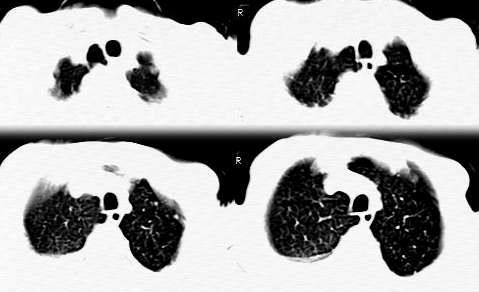

其次是定性问题:本例征象:1 右侧胸腔巨块内见不规则钙化,征象同前述;2 左肺门肿块;3 肺内多发结节及支血束结节状改变;4 右上叶支气管受压无壁厚或阻塞;5 无肺纤维化表现;6 右侧胸液,心包无异常;7 骨质或腋窝无异常。结合老年患者,病史较长,以上征象集中在一起需鉴别于以下疾病:

定位,应定为中纵隔中、下区。理由:大部边缘光滑,前联合线移向患侧。肿块大部分位于中纵隔区

定性,考虑肿块大+胸腔积液+左下肺小结节+68岁考虑恶性可能大